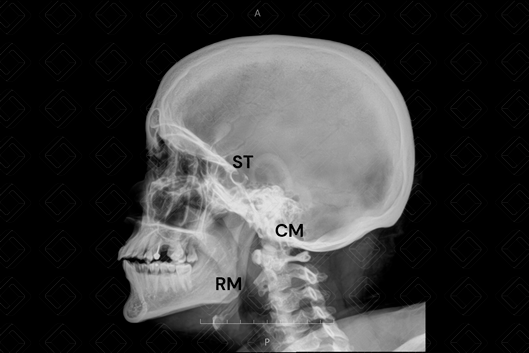

Radiografia do crânio estudo em AP e perfil (são as incidências básicas e mínimas para a realização do exame) .

Legenda das siglas: AE = asa menor esfenoide; CE = células etmoidais; CM = células mastoideas; RM = ramo mandibular; [cms-watermark] SF = seio frontal; ST = sela túrcica.